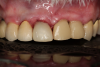

Fig 12. Six months after cementation.

Figure 12

After 4 months of healing and integration of the bone around the implant, the digital workflow was initiated to develop the abutment and treatment plan. Another analog impression was made with an impression post and polyvinyl impression. The laboratory scanned the impression and digitized it to create the emergence profile of the milled titanium abutment and the final restoration (Figure 10 and Figure 11). The patient had a considerably thick soft-tissue profile, allowing a milled titanium abutment. The decision to use a titanium abutment was based on the patient's occlusion and propensity to fracture teeth or restorations. The virtual model was gray because the scanner does not recognize the color of the analog impression. The virtual final abutment and crown were approved and fabrication completed. The final restoration met the patient's esthetic values and his ability to function (Figure 12 and Figure 13).